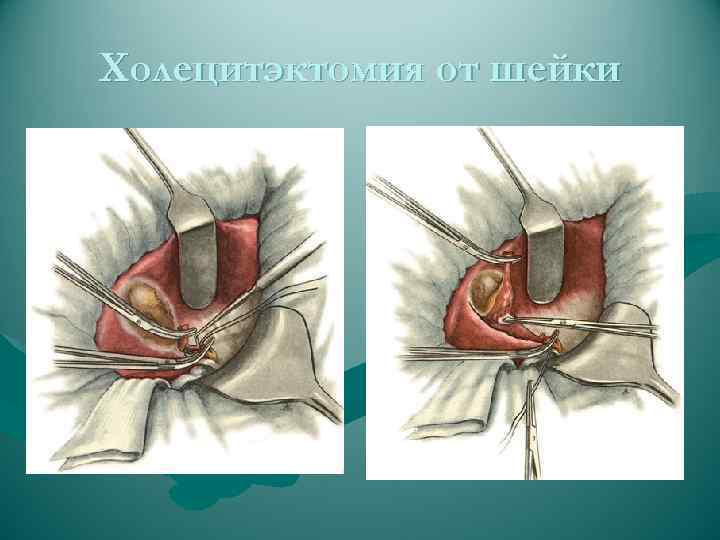

ВИДЫ ОПЕРАЦИЙ НА ЖЕЛЧНЫХ ПУТЯХ 1. Холецистотомия 2. Холецистостомия 3. Холецистэктомия - от дна (антеградная) преимущество • надежная идентификация отдельных элементов шейки пузыря недостаток • большая кровоточивость - от шейки (ретроградная) преимущество • малая кровоточивость при выделении желчного пузыря (перевязка a. cystica); • предотвращается возможность проталкивания мелких камней из пузыря в ductus choledochus (перевязка d. cysticus) - комбинированный способ 4. Холецистоэнтеростомия 5. Холедохотомия - эксплоративная (во время холецистэктомии) - трансдуоденальная 6. Холедоходуоденостомия 7. Папиллосфинктеротомия

ВИДЫ ОПЕРАЦИЙ НА ЖЕЛЧНЫХ ПУТЯХ 1. Холецистотомия 2. Холецистостомия 3. Холецистэктомия - от дна (антеградная) преимущество • надежная идентификация отдельных элементов шейки пузыря недостаток • большая кровоточивость - от шейки (ретроградная) преимущество • малая кровоточивость при выделении желчного пузыря (перевязка a. cystica); • предотвращается возможность проталкивания мелких камней из пузыря в ductus choledochus (перевязка d. cysticus) - комбинированный способ 4. Холецистоэнтеростомия 5. Холедохотомия - эксплоративная (во время холецистэктомии) - трансдуоденальная 6. Холедоходуоденостомия 7. Папиллосфинктеротомия

ЭТАПЫ ОПЕРАЦИИ ТИПИЧНОЙ ХОЛЕЦИСТЭКТОМИИ 1. Лапаротомия 2. Обнажение желчного пузыря 3. Выделение, перевязка и пересечение ductus cysticus и a. cystica 4. Выделение желчного пузыря из его ложа и удаление 5. Перитонизация ложа пузыря 6. Зашивание раны брюшной стенки ЭТАПЫ ОПЕРАЦИИ ЛАПАРОСКОПИЧЕСКОЙ ХОЛЕЦИСТЭКТОМИИ 1. Оперативный доступ 2. Выделение желчного пузыря из сращений с окружающими тканями 3. Выделение, клипирование и пересечение пузырного протока и пузырной артерии 4. Отделение желчного пузыря от печени 5. Извлечение желчного пузыря из брюшной полости

ЭТАПЫ ОПЕРАЦИИ ТИПИЧНОЙ ХОЛЕЦИСТЭКТОМИИ 1. Лапаротомия 2. Обнажение желчного пузыря 3. Выделение, перевязка и пересечение ductus cysticus и a. cystica 4. Выделение желчного пузыря из его ложа и удаление 5. Перитонизация ложа пузыря 6. Зашивание раны брюшной стенки ЭТАПЫ ОПЕРАЦИИ ЛАПАРОСКОПИЧЕСКОЙ ХОЛЕЦИСТЭКТОМИИ 1. Оперативный доступ 2. Выделение желчного пузыря из сращений с окружающими тканями 3. Выделение, клипирование и пересечение пузырного протока и пузырной артерии 4. Отделение желчного пузыря от печени 5. Извлечение желчного пузыря из брюшной полости

ЭТАПЫ ОПЕРАЦИИ ТИПИЧНОЙ ХОЛЕЦИСТЭКТОМИИ ( от шейки) 1. Лапаротомия 2. Обнажение желчного пузыря 3. Выделение, перевязка и пересечение ductus cysticus и a. cystica 4. Выделение желчного пузыря из его ложа и удаление 5. Перитонизация ложа пузыря? ? ? 6. Зашивание раны брюшной стенки ЭТАПЫ ОПЕРАЦИИ ТИПИЧНОЙ ХОЛЕЦИСТЭКТОМИИ ( от дна) 1. Лапаротомия 2. Обнажение желчного пузыря 3. Выделение желчного пузыря из его ложа и удаление 4. Выделение, перевязка и пересечение ductus cysticus и a. cystica 5. Перитонизация ложа пузыря? ? ? 6. Зашивание раны брюшной стенки

ЭТАПЫ ОПЕРАЦИИ ТИПИЧНОЙ ХОЛЕЦИСТЭКТОМИИ ( от шейки) 1. Лапаротомия 2. Обнажение желчного пузыря 3. Выделение, перевязка и пересечение ductus cysticus и a. cystica 4. Выделение желчного пузыря из его ложа и удаление 5. Перитонизация ложа пузыря? ? ? 6. Зашивание раны брюшной стенки ЭТАПЫ ОПЕРАЦИИ ТИПИЧНОЙ ХОЛЕЦИСТЭКТОМИИ ( от дна) 1. Лапаротомия 2. Обнажение желчного пузыря 3. Выделение желчного пузыря из его ложа и удаление 4. Выделение, перевязка и пересечение ductus cysticus и a. cystica 5. Перитонизация ложа пузыря? ? ? 6. Зашивание раны брюшной стенки

Холецитэктомия от шейки

Холецитэктомия от шейки